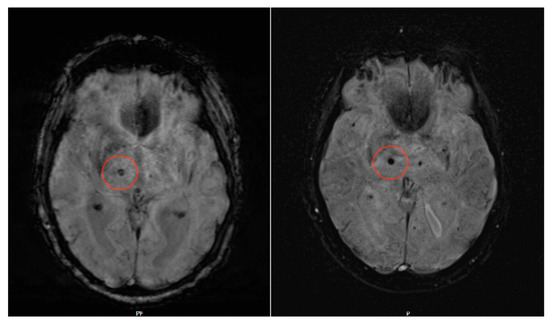

Our study shows that detection of microbleeds in SWI MRI sequences at a field strength of 0.55 T is possible with the same specificity and sensitivity compared to conventional 1.5 T MRI (for sample sequences, see Figure 2). Moreover, Likert ratings for the subjective evaluation of spatial resolution and contrast resolution were not significantly different for both 0.55 T and 1.5 T sequences, whereas for SWI noise, 0.55 T sequences were even superior.

Figure 2.

SWI lesion of the right thalamus. In both images (left, axial 1.5 T SWI sequence; right, axial 0.55 T SWI sequence), this lesion is clearly detectable, although it is even better delineated in the 0.55 T dataset.